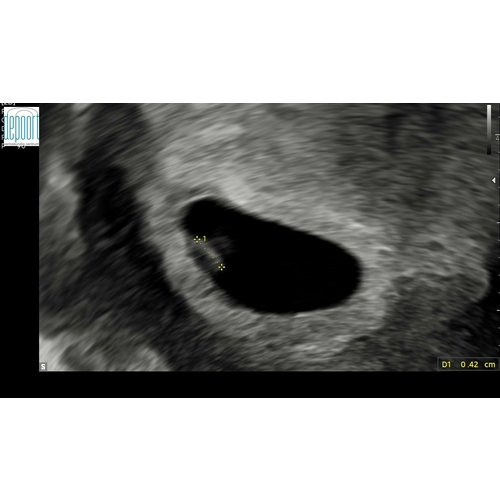

Op de echo kon je wel goed het vruchtzakje zien, maar was te klein voor 6 weken, hij was 11mm.

Ik ben terug gezet op 5+3. Verder konden ze nog niks vinden in de vruchtzak. Nu vrijdag moet ik weer heen en ben dan 6+2 en ik hoop echt dat we dan wat gaan zien. 🍀

Eindstand kregen we dit beeld, daarnaast was het een uitwendige echo (meestal rond dit termijn worden inwendige echo’s gemaakt, dan is er net wat meer te zien)

De echoscopiste zei tegen mij: het kan zijn dat je minder ver bent dan je denkt maar hou maar rekening met een miskraam.